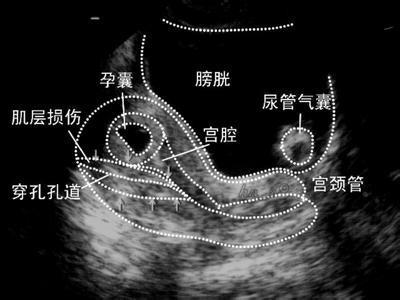

1.子宫穿孔

任何手术都是有风险的,哪怕是小小的人工流产。人工流产会有哪些并发症呢?子宫穿孔、肠道损伤。子宫看起来很结实,能被胎儿撑的如气球般也不会破 裂,但实际上子宫有非常的脆弱。人工流产中,时常有探针和吸头,穿过了子宫肌层进入了腹腔。子宫的肌层是有收缩功能的,大多数的子宫穿孔并不会致命,但人 工流产是用负压吸引器的,如果这个负压吸头进入了腹腔,那么可能将肠管吸进来,造成肠管的损伤。曾经有一家医院发生过这样的事件。术中感觉到子宫有损伤, 患者也收入院观察,但开始的时候不能判断是否有肠道的损伤。观察一天后,患者发热、感染、最后休克,花了十几万元、做了手术、住在ICU一个多月猜康复。因为肠道内的细菌很快就会感染腹腔造成感染性的休克。 也许你会说这是医院的责任医生的责任,但无论谁的责任,受伤害的都是患者。而且这种并发症的发生,无论医生怎么小心、怎么技术娴熟、怎么有责任心,都不能100%避免,避免的方法就是不去做人工流产。

图片来源于网络